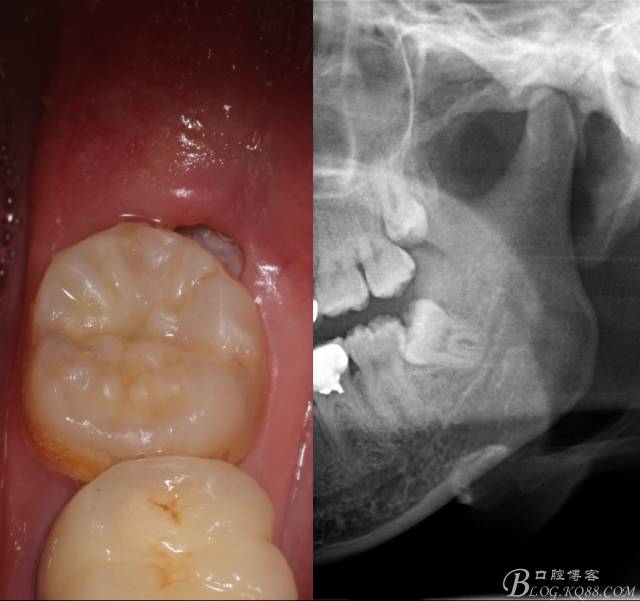

檢查:(1)37牙合面齲,卡探針.         (2)38近中埋伏阻生

X全景片示38近中三類阻生,非融合根,近中根壓下頜管,37遠(yuǎn)中鄰面中齲樣影像。

診斷:(1)37中齲        (2)38近中阻生

先分析智齒的情況,口內(nèi)直觀是半個(gè)牙尖都沒露出來,差一點(diǎn)就完全埋伏了。磨牙后墊的可操作面積中規(guī)中紀(jì),X全景片示三類阻生,根冠比例是1:1,非融合根,近中根壓下頜管。